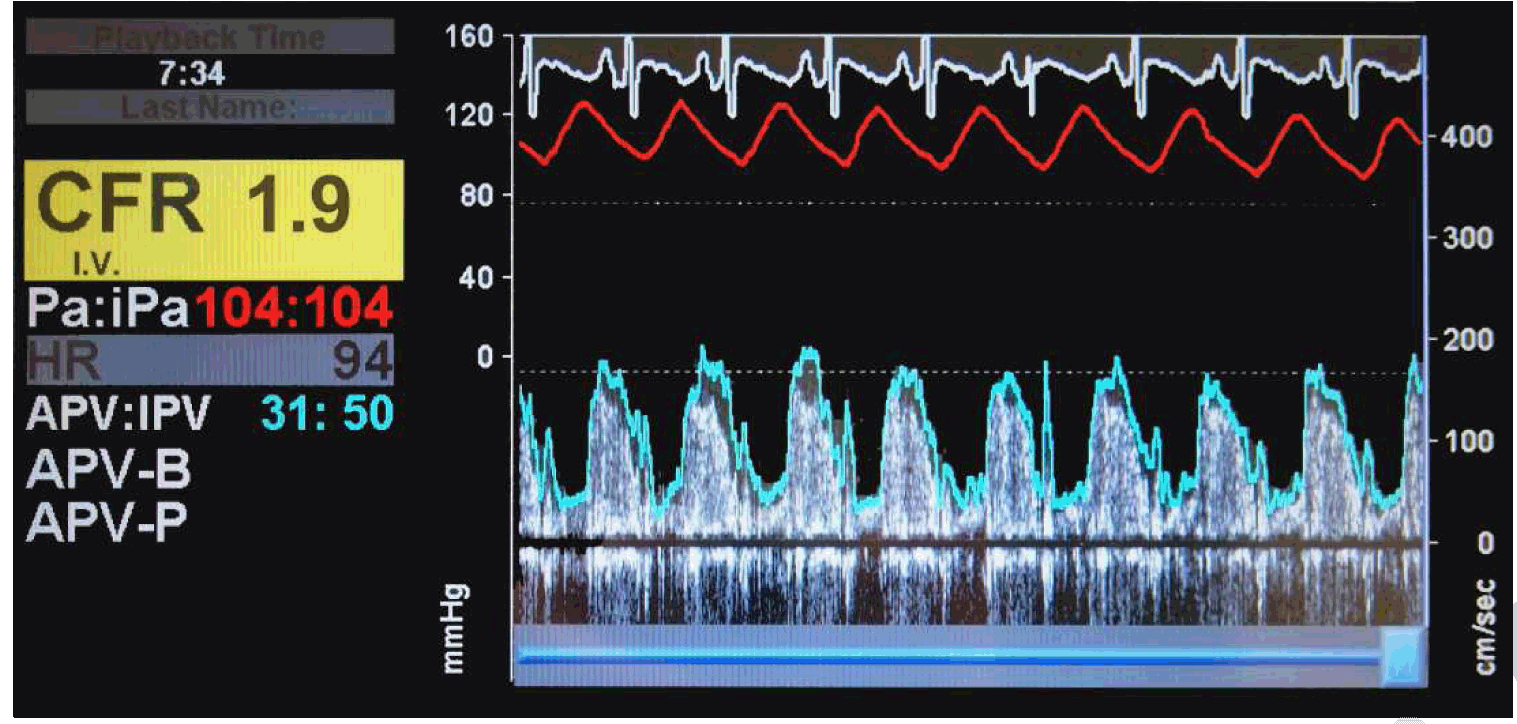

MCD was diagnosed by invasive coronary reactivity testing as previously published (Figure 1) [6]. She had normal coronary arteriography without luminal irregularity and left ventricular end-diastolic filling pressure was elevated at 17 mmHg. Coronary flow reserve (CFR) in response to adenosine (Figure 2) was abnormal at 1.9 (normal >2.5), coronary blood flow response to acetylcholine was mildly abnormal at 48% increase (normal is =50% increase), coronary artery diameter dilation response to acetylcholine was markedly abnormal at 22% constriction (normal is dilation >0%), and nitroglycerin response was normal at 46% dilation (normal >20%) as depicted in Figure 1 and Figure 2.

Figure 2: Intracoronary Doppler blood flow velocity waveforms in response to intracoronary adenosine. Coronary flow reserve is the ratio of average peak velocities before and after adenosine administration. Adenosine tests nonendothelial-dependent microvascular function.